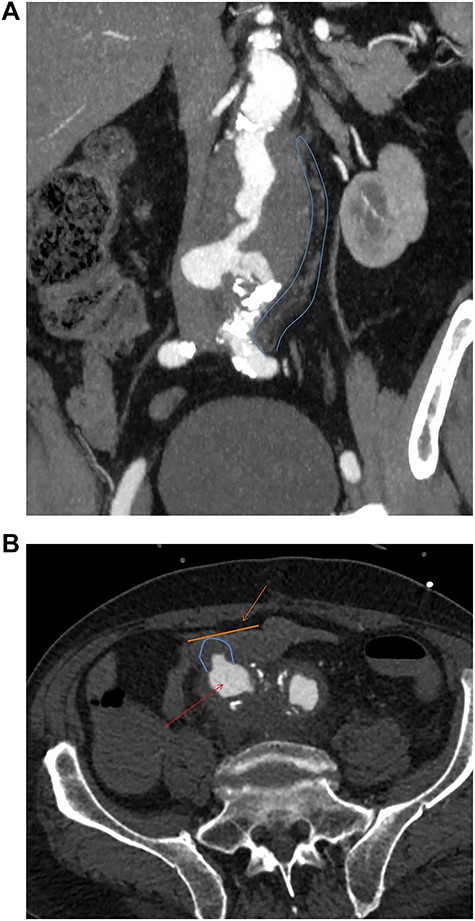

One year after the initial operation, the patient reattended the emergency department with frank haematemesis, rectal bleeding and sepsis in acute haemorrhagic shock. Following resuscitation, an oesophago-gastro duodenoscopy (OGD) revealed fresh blood but no upper GI source of bleeding. Computed tomography (CT) imaging identified a duodenal AEF (Fig. 1a) consistent with communication with the suture line of native aortic-prosthesis. AEF is located 45 mm distal to the lowest (left) branch of the renal artery. The patient successfully underwent emergency relining of the infrarenal aorta into the original graft with a 28 × 43mm COOK® main body extension graft with good overlap (Fig. 1b).

(a) Axial thick slice of a CT with IV contrast in the arterial phase shows the lumen of the surgical graft (yellow arrow), clear contrast opacification within the fistula (red line and arrow) and the duodenum (blue line and arrow) consistent with active haemorrhage; (b) sagittal reconstruction of a CT with IV contrast in the arterial phase showing the overlapping aortic stent grafts inserted to exclude the AEF from the circulation.